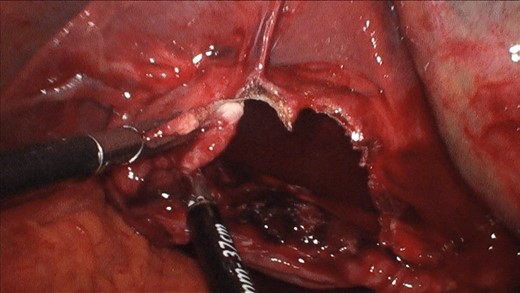

After placing a 10 mm umbilical port, we found signs of diffuse peritonitis and a dark brown ascites throughout the abdominal cavity, but mainly in the right quadrants, from the subdiaphragmatic to the pelvic region. The source of the ascites was a large cystic lesion in segment VI of the liver that ruptured next to the gallbladder infundibulum (Fig. 3). There was no visible blood, bile or pus, and the rest of the abdominal exploration was unremarkable. After placing three additional 5 mm ports (two in the right upper quadrant and one subxiphoid), we proceeded with the deroofing of the ruptured cyst using a laparoscopic vessel-sealing device (Figs 4 and 5). The inner surface of the cyst was carefully inspected and no cystobilliary communication was found. Samples of the ascites were sent for citology and microbiology. A thorough peritoneal lavage was performed, and the abdominal cavity was drained using two 15Fr Blake drains. The total operative time was 95 min and there was a minimal blood loss.

Laparoscopic deroofing of the cyst using vessel-sealing device.